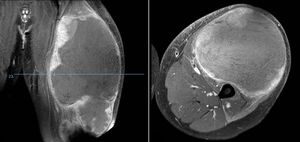

Tumoración palpable dolorosa (fig. 1) junto con enrojecimiento y calor constituye la forma de presentación más frecuente. Hasta una quinta parte presenta además síntomas constitucionales debidos a la liberación de citoquinas10 tales como fiebre, astenia, anorexia y pérdida de peso1,3, que incluso pueden inducir al diagnóstico erróneo de una osteomielitis4. El estadio más frecuente de presentación es el IIB de la American Joint Committe on Cancer (AJCC)4 y alrededor de un 20% presentan metástasis al diagnóstico, siendo el pulmón la localización más frecuente, pero se estima que muchos más presentan micrometástasis al diagnóstico que no pueden ser detectadas con las técnicas diagnósticas actuales. Estas serían las responsables del mal pronóstico de los Ewing catalogados como «localizados»3,10,11.

Del total de sarcomas, 32 (78,05%) correspondieron a Ewing de tipo óseo y los 9 restantes (21,95%) a Ewing extraesquelético. Las localizaciones del grupo óseo se repartieron entre: fémur (10 casos, 31,25%), columna (8 casos, 25%), peroné (4 casos, 12,5%), pelvis (3 casos, 9,38%), calcáneo (2 casos, 6,25% figura 2), tibia (2 casos, 6,25%), húmero (2 casos, 6,25%) y 5.° metatarsiano (1 caso, 3,13%). Uno de los pacientes del grupo óseo debutó con una fractura patológica a nivel diafisario femoral, y otro paciente sufrió otra fractura patológica también femoral durante los primeros ciclos de quimioterapia neoadyuvante. En lo que al grupo extraesquelético se refiere, los emplazamientos fueron: muslo (3 casos, 33,33%), pierna (2 casos, 22,22%), hueco poplíteo (2 casos, 22,22%), paravertebral (1 caso, 11,11%) y epidural (1 caso, 11,11%). En la tabla 1 se expone un resumen demográfico de la serie de pacientes.

Sarcoma de Ewing de calcáneo, imágenes de radiología convencional (A) y de RM (B). Fue tratado mediante resección y reconstrucción con aloinjerto (C). Radiografía tras 6 años de evolución (D) en la que se aprecia artrodesis consolidada calcáneo-astragalina y calcáneo-cuboidea y fractura-avulsión de tuberosidad posterior ocurrida en el primer año tratada de manera conservadora porque no generó alteración funcional.